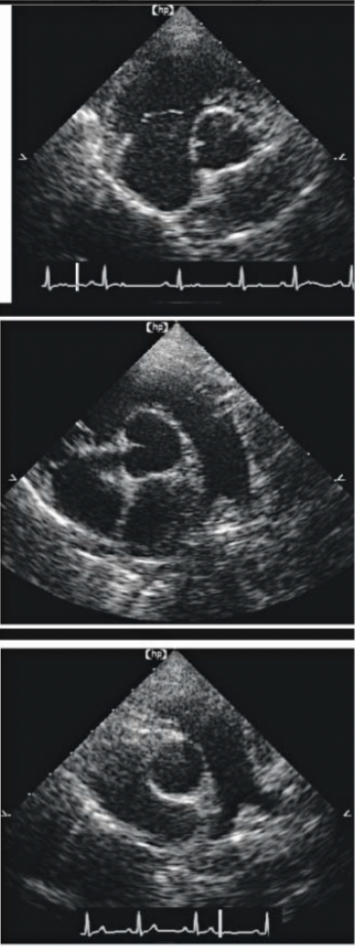

Name the echo view AND structures

RPS SHORT AXIS